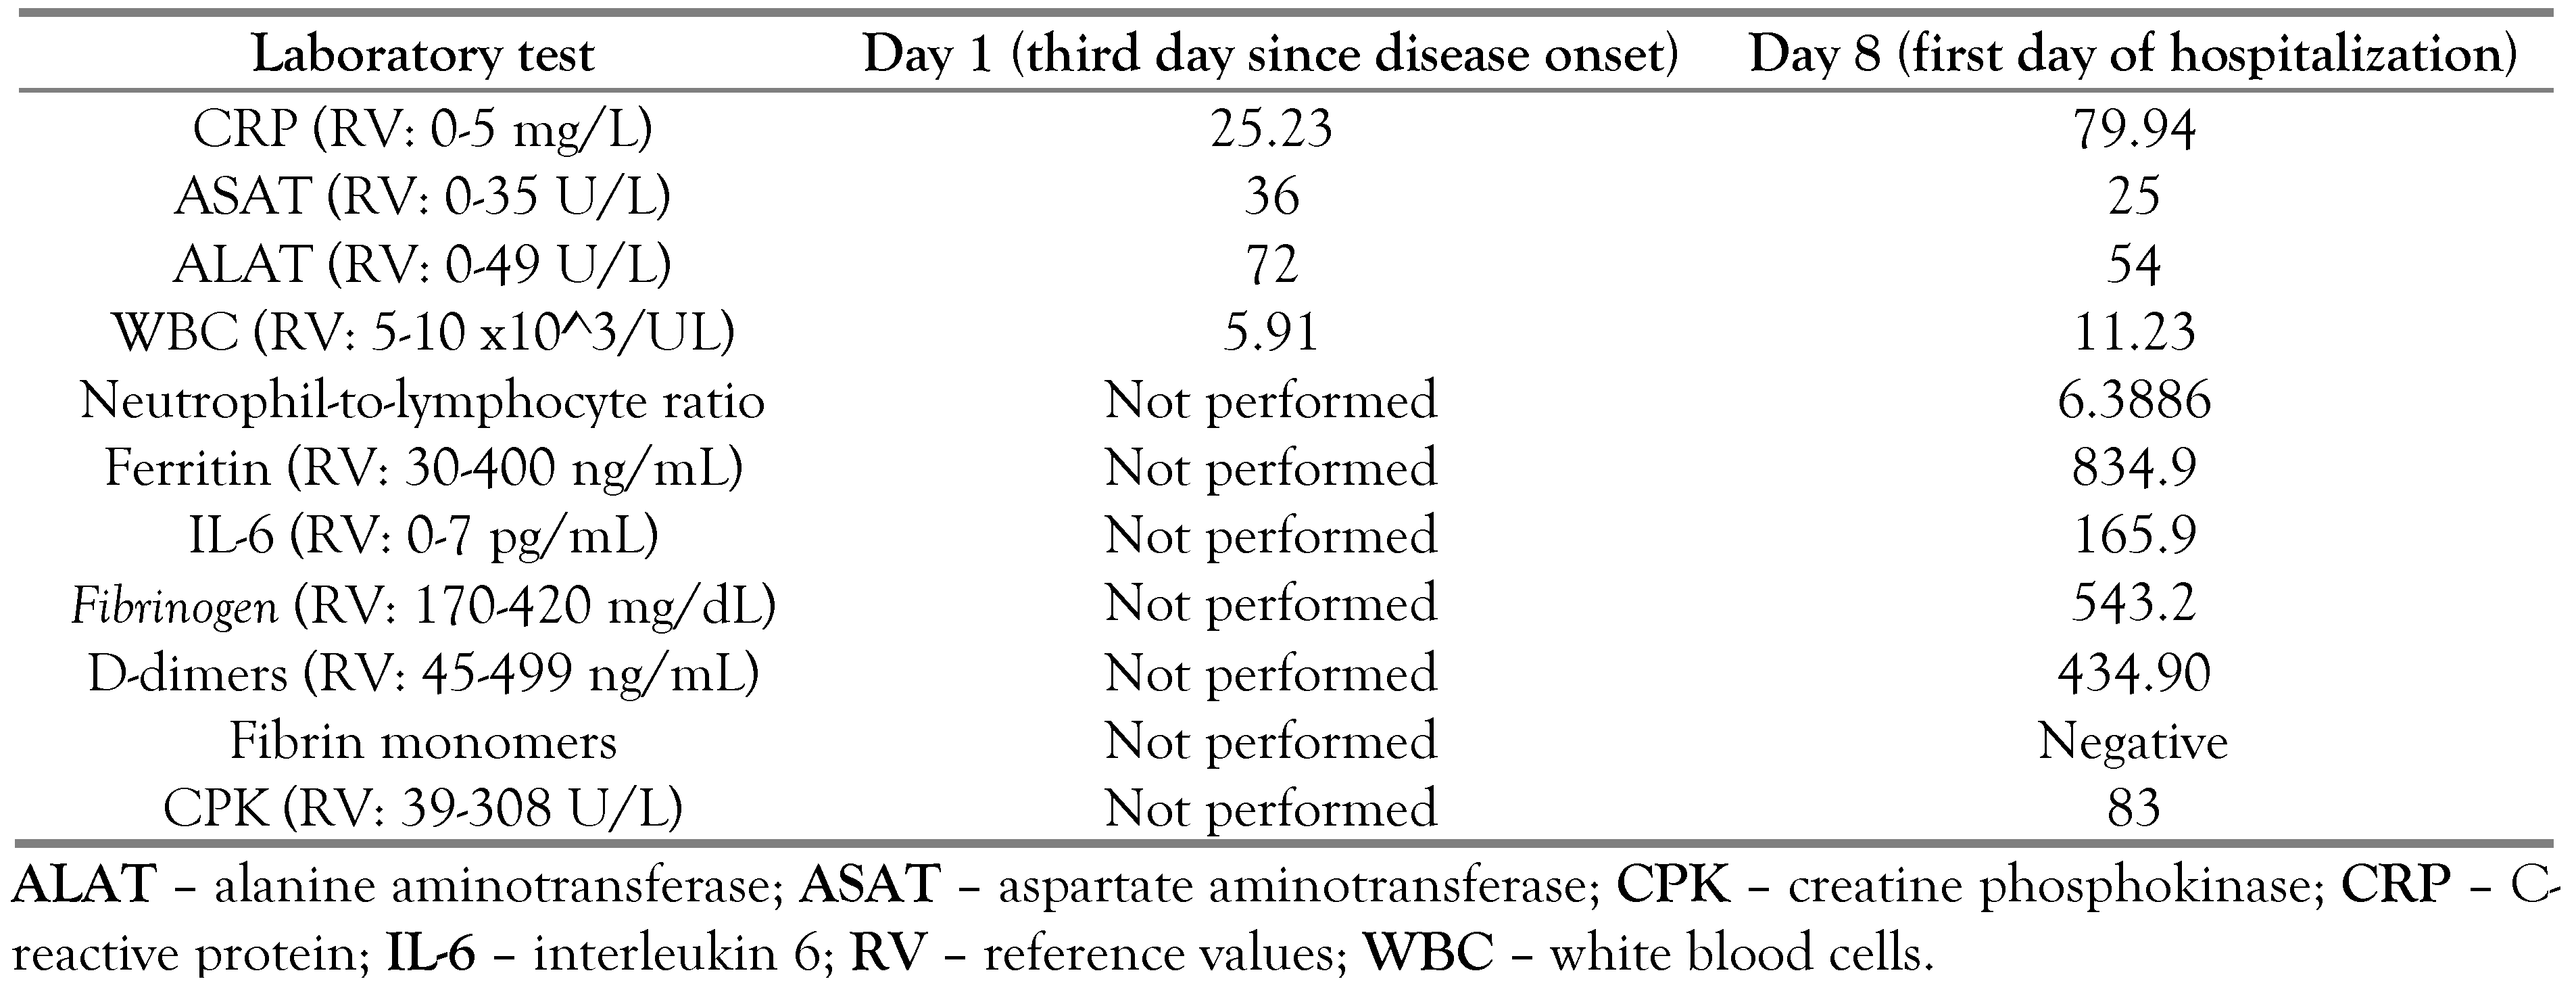

|